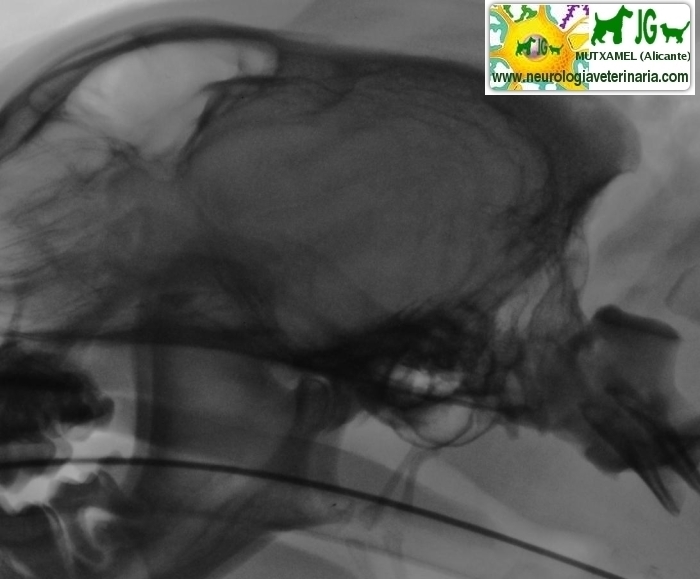

Radiografía simple (sin contrastes) | |||||||||

Radiografía digitalizada de cachorro de Siberian Husky con severo trauma craneal |